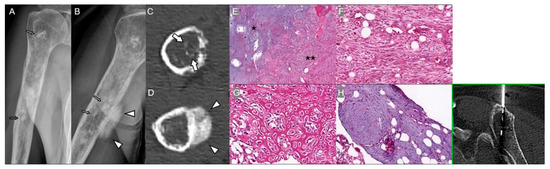

Malignant Transformation of Musculoskeletal Lesions with Imaging–Pathology Correlation—Part 1: Bone Lesions

by Hyang Sook Jeong, Seul Ki Lee, Jee-Young Kim, Changyoung Yoo and Min Wook Joo

Background/Objectives: Malignant transformation of bone lesions, although rare, poses a major diagnostic and clinical challenge. Common benign lesions (e.g., osteochondroma, enchondroma, fibrous dysplasia, giant cell tumor), non-tumorous conditions (e.g., chronic osteomyelitis, irradiated bone, infarction), and low-grade malignancies (e.g., low-grade osteosarcoma, chondrosarcoma) can evolve [...] Read more.

Background/Objectives: Malignant transformation of bone lesions, although rare, poses a major diagnostic and clinical challenge. Common benign lesions (e.g., osteochondroma, enchondroma, fibrous dysplasia, giant cell tumor), non-tumorous conditions (e.g., chronic osteomyelitis, irradiated bone, infarction), and low-grade malignancies (e.g., low-grade osteosarcoma, chondrosarcoma) can evolve into aggressive malignancies through distinct genetic, molecular, and microenvironmental pathways. Recognizing early malignant transformation on imaging is crucial for timely diagnosis and management. Methods: This review synthesizes current imaging characteristics, pathologic mechanisms, and clinical risk factors associated with malignant transformation of benign and low-grade malignancy bone lesions. Results: Atypical imaging findings and inaccurate biopsies can delay diagnosis. Aggressive features—such as cortical destruction, heterogeneous enhancement, and loss of internal matrix—should prompt further pathologic evaluation. Advanced imaging and a multidisciplinary approach with integrated clinicoradiologic–pathologic review are essential to minimize missed diagnoses. Patients with risk factors such as genetic syndromes, prior denosumab therapy, inadequate surgery, or prior radiation therapy require close monitoring or timely intervention. Conclusions: Radiologic–pathologic correlation remains central to distinguishing benign from malignant lesions. This review article emphasizes a comprehensive imaging-pathology overview of benign and low-grade malignancy bone lesions with malignant potential, aiming to improve diagnostic accuracy and outcomes in orthopedic oncology. Full article